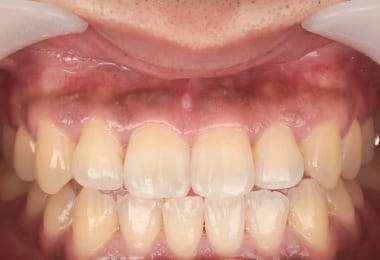

Before

1週間後

After

2週間後